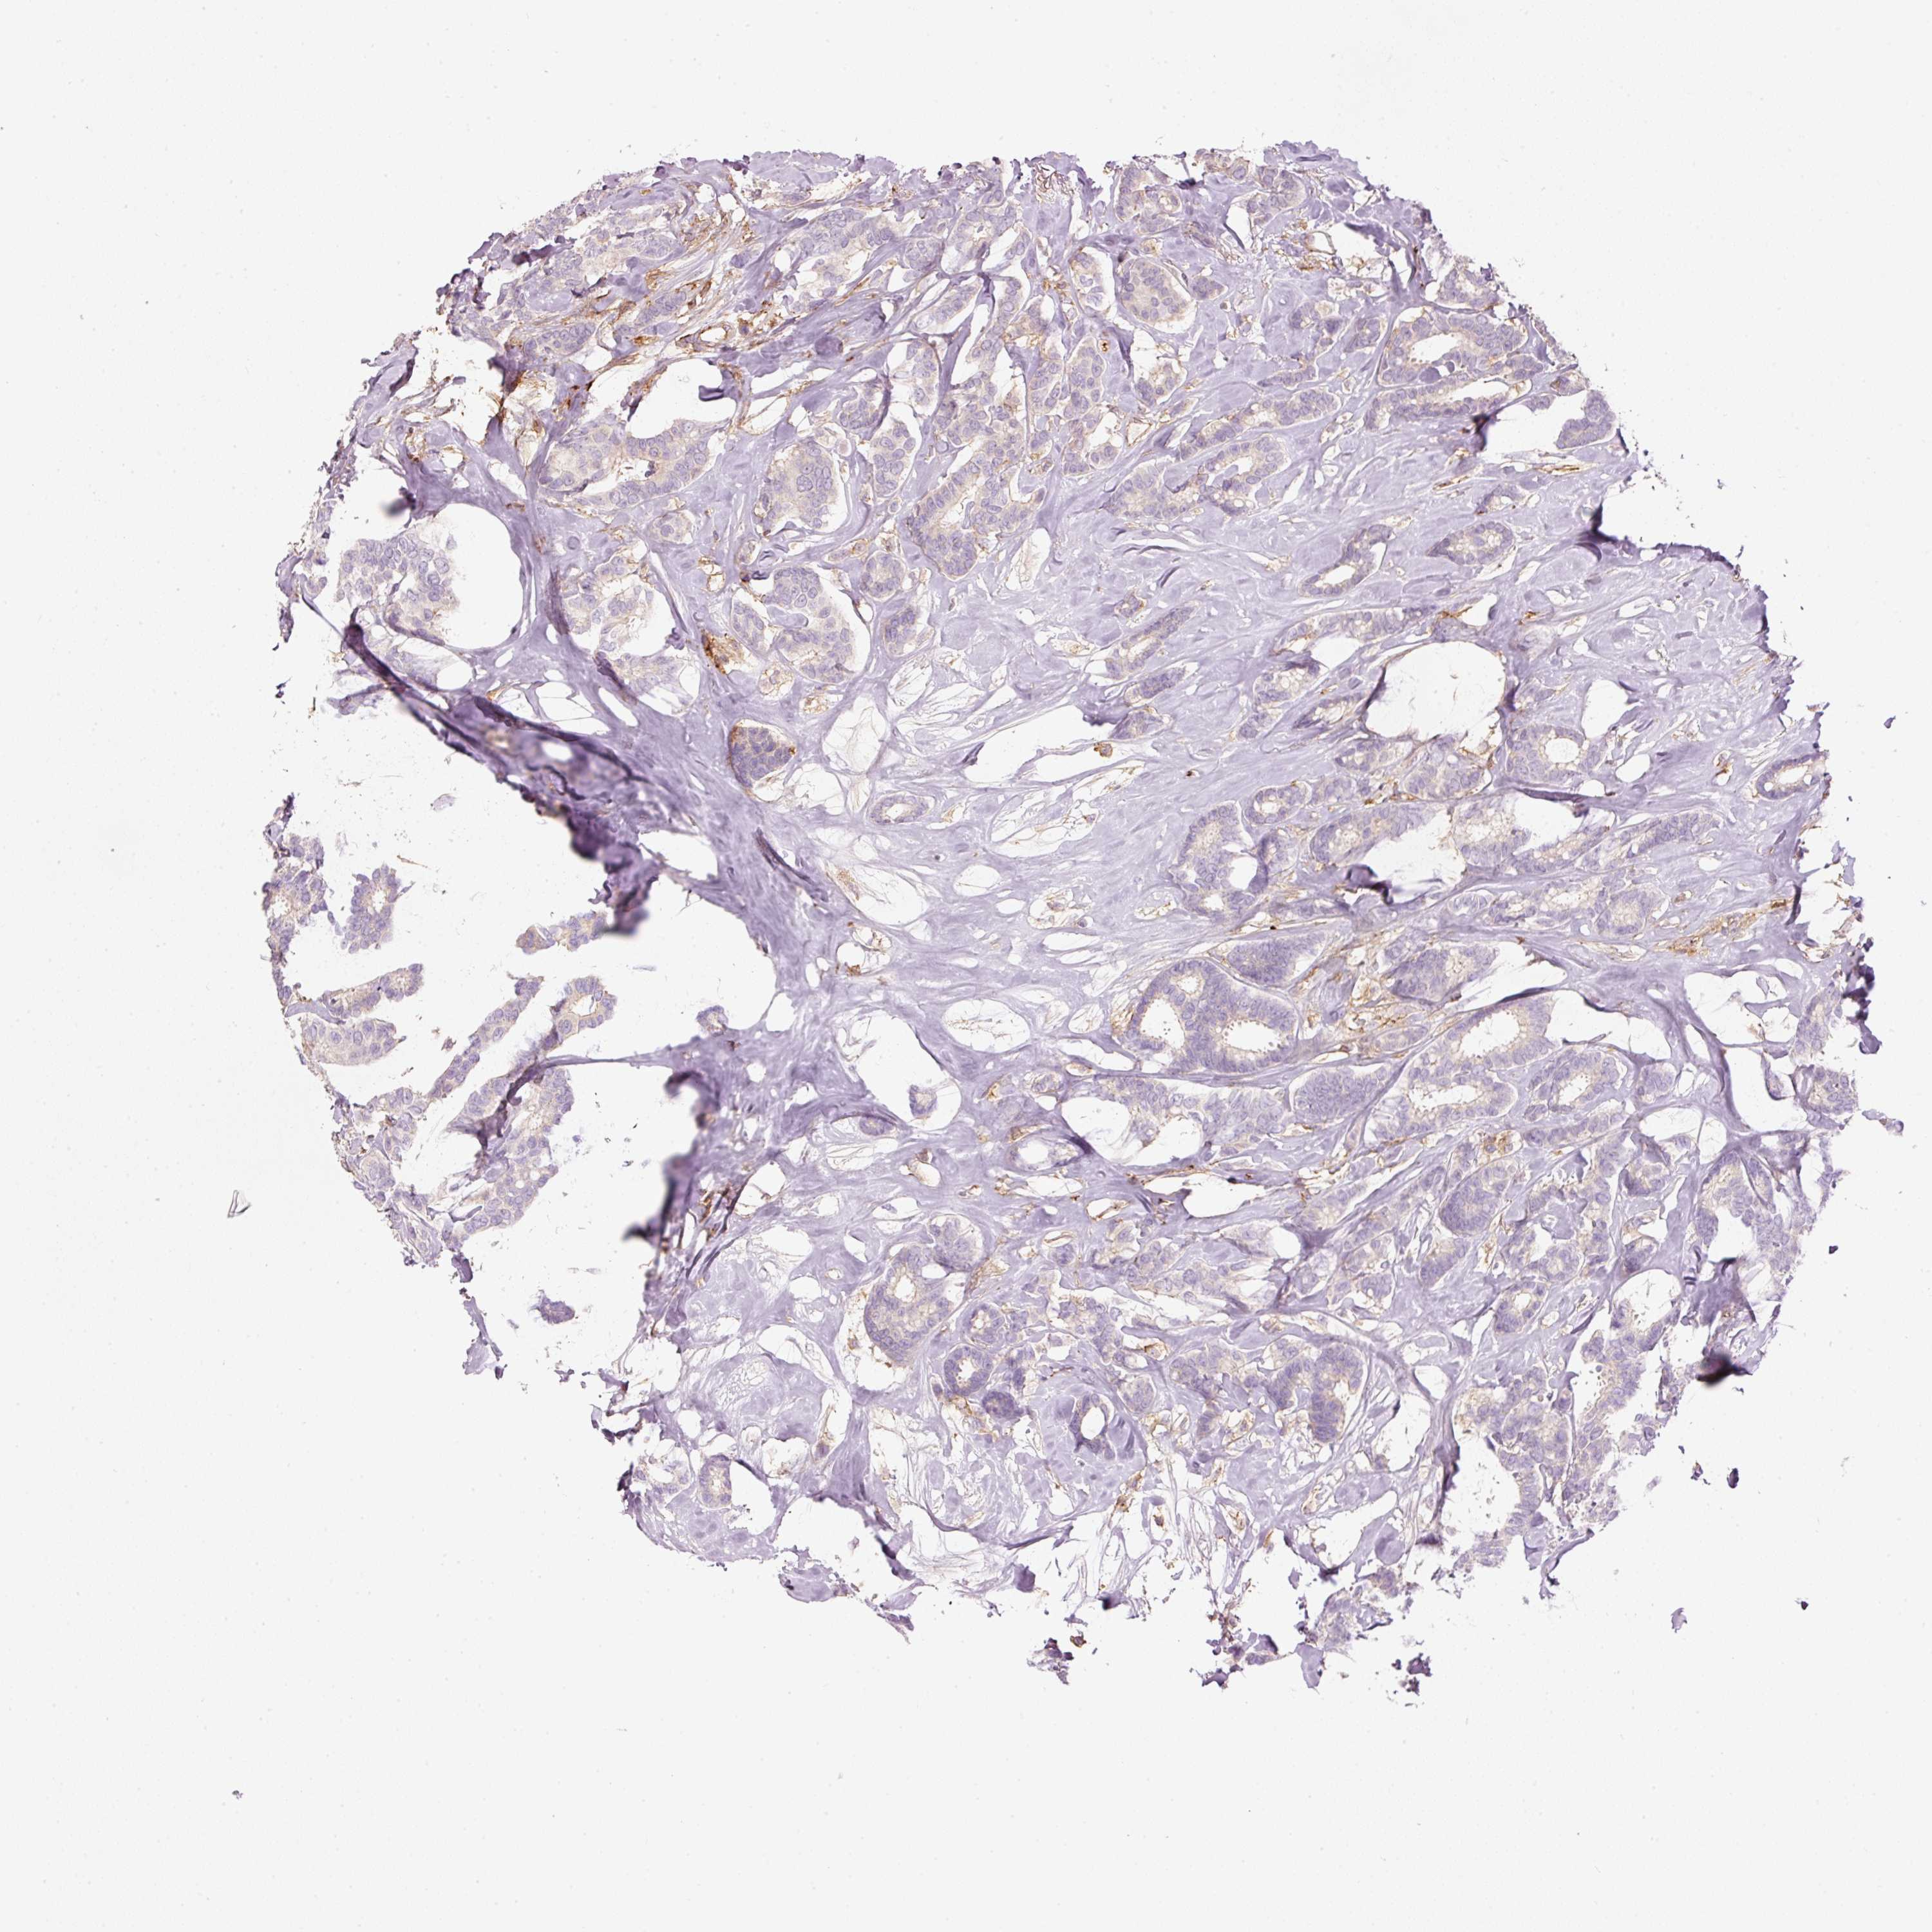

CANCER BREAST CANCER Show tissue menu

BRCA TCGA BRCA VALIDATION PROTEIN EXPRESSION

ANTIBODIES

AND

VALIDATION